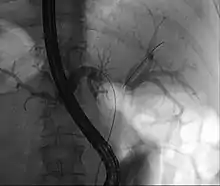

Klatskin tumor during ERCP. Wires were inserted into the left and right biliary systems. Both parts were injected through a tube with contrast, but there is no contrast visible in the area of confluence of the two systems | |